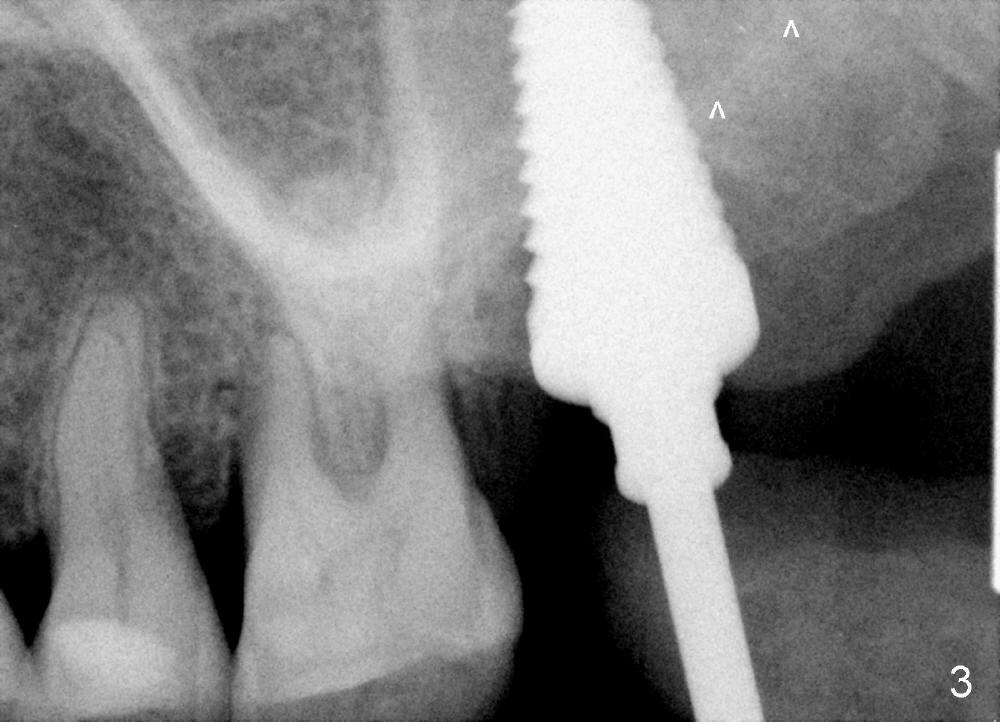

A 56-year-old female has recurrent infection and buccal gingival recession (Fig.1 *) after root canal therapy in the upper left 2nd molar (Fig.2). The extraction socket is single and large. Osteotomy forms by using a series of osteotomes (2-5 mm in diameter) mesiopalatal to the center of the socket. The sinus floor is thin (approximately 2-3 mm). The osteotomy is further enlarged by inserting 4.5-8 mm taps at the depth between 14 and 17 mm from the gingival margin. The last tap has barely achieved stability (Fig.3). It appears that the tap has almost obliterated the socket. Allograft is pushed into the sinus before placement of a 8x17 mm implant. The insertion torque is between 15 and 20 Ncm (Fig.4). The gingiva-level implant is slightly subgingival except buccal (Fig.5). To facilitate buccal gingival re-growth and cover the exposed implant surface, bone graft is placed subgingival (Fig.5 ^). The gingival sulcus is closed partially by placement of a thin strip of collagen membrane (not shown). The wound is protected by applying perio dressing.